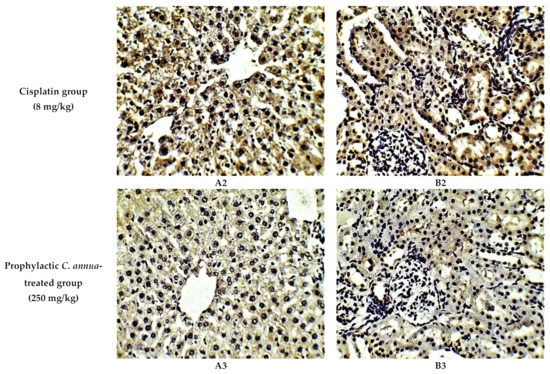

The protective effect of C. annua extract against cisplatin sparked inflammation and apoptosis in renal and hepatic tissues was further confirmed by immunohistochemistry (IHC) where the expression of both IL-1β (an inflammation marker) and caspase-3 (an apoptosis marker) were investigated. Cisplatin group exhibited pronounced expression of IL-1β and caspase-3 in both renal and hepatic tissues of cisplatin treated group compared to the normal control group. Pretreatment with C. annua extract before cisplatin injection has noticeably reduced IL-1β and caspase-3 expression in both kidney and liver tissues in comparison with the cisplatin group (Figure 3, Figure 4, Figure 5).

Representative photomicrographs (×400) of immuno-histochemical staining of caspase-3 in liver (A) and kidney (B) tissues of the experimental groups. (A1) liver tissues of normal control group, (A2) liver tissues of cisplatin group, (A3) liver tissues of Prophylactic C. annua- treated group, (B1) kidney tissues of normal control group, (B2) kidney tissues of cisplatin group, (B3) kidney tissues of Prophylactic C. annua- treated group.

Figure 5.

(A) Level of IL-1β expression in liver and kidney tissues of the experimental groups. Positive proportions of IL-1β expression were increased significantly in liver and kidney of cisplatin treated rats compared to the normal control and C. annua pretreated group. (B) Level of caspase-3 expression in liver and kidney tissues of the experimental groups. Positive proportions of caspase-3 expression were elevated remarkably in liver and kidney of cisplatin treated rats compared to the normal control and C. annua pretreated group. Data are represented as mean ± SE and analyzed using ANOVA followed by Bonferroni’s post-hoc test at p value < 0.05, n = 15 for each group. a indicates the presence of significant difference from normal control group, b indicates the presence of significant difference from cisplatin group.